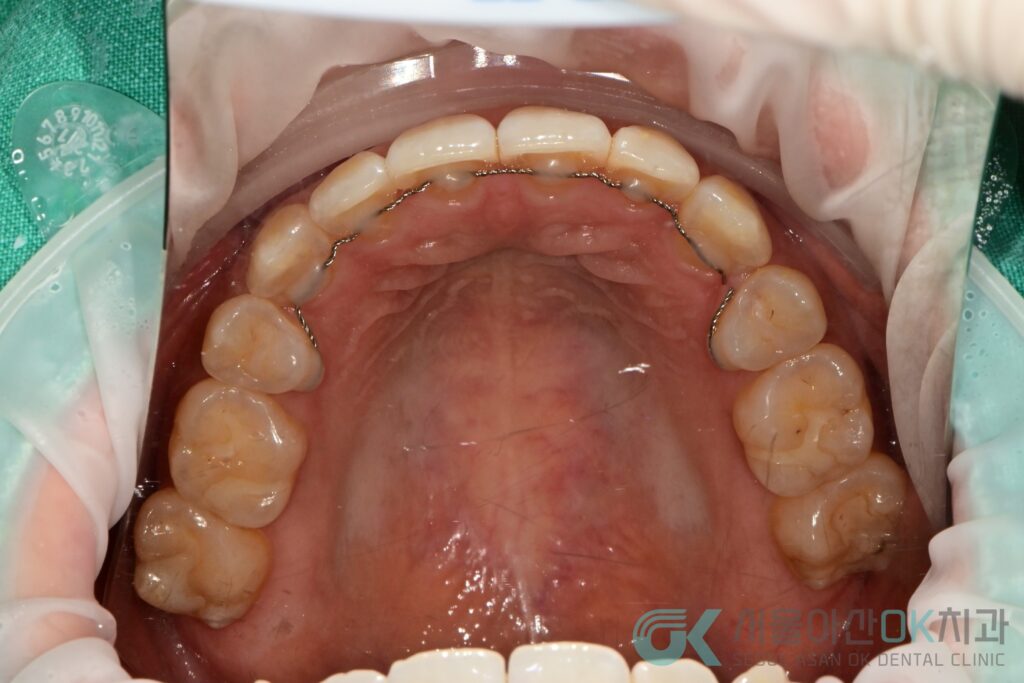

2025-07-26에 ISQ 80/76(충분히 양호한 고정도)

ScanBody로 인상(스캔)

커스텀 어버트먼트 + 지르코니아 크라운 제작 의뢰로 보철 단계로 넘어갔습니다.

6) 최종 단계: 나사 유지형 지르코니아 보철(SCRP) 장착

2025-08-09 #36 SCRP 타입(나사로 고정하는 보철) 장착을 시행했고,

스크류 타이트닝(기록상 30N) 교합 조정 홀 임시 충전 후,

2025-08-16에 레진으로 최종 홀 충전까지 마무리했습니다.